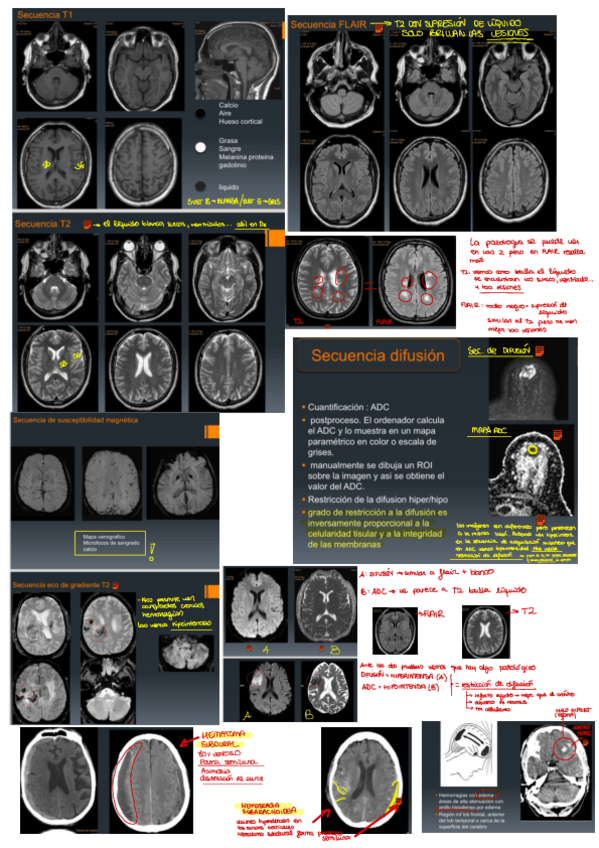

He publicado nuevos apuntes de 3º ESTUDIO POR LA IMAGEN: Apuntes-neuro.pdf

10 páginas

He publicado nuevos apuntes de 3º ESTUDIO POR LA IMAGEN: Resumen-Neuro-Rx-parte-2.pdf

13 páginas

He publicado nuevos apuntes de 3º ESTUDIO POR LA IMAGEN: Resumen-Neuro-Rx-parte-1.pdf